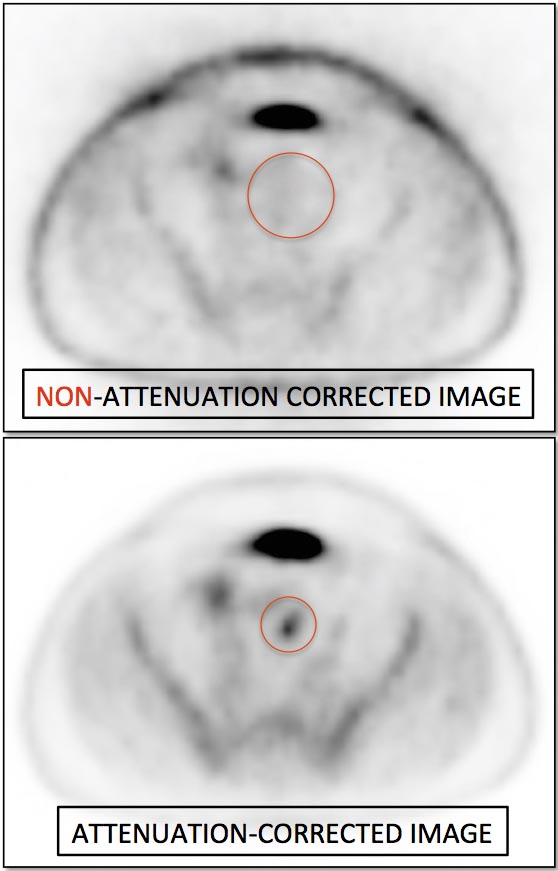

Attenuation Correction (AC) Artifacts:

On occasion (typically in older PET/CT machines), attenuation correction of PET images can result in falsely elevated metabolic activity in regions of high CT density (e.g. metallic devices, oral contrast, calcification). In such cases, these areas must be reviewed on the NAC (non-attenuation correction) images. If these regions are not also hypermetabolic on the NAC images, then their apparent increased FDG-uptake on the AC images is artifactual. [FIG. 10] [FIG. 11]